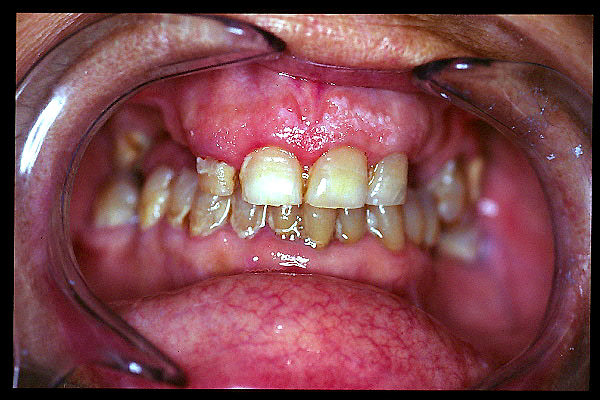

CM Caries, patología periodontal, desgaste.